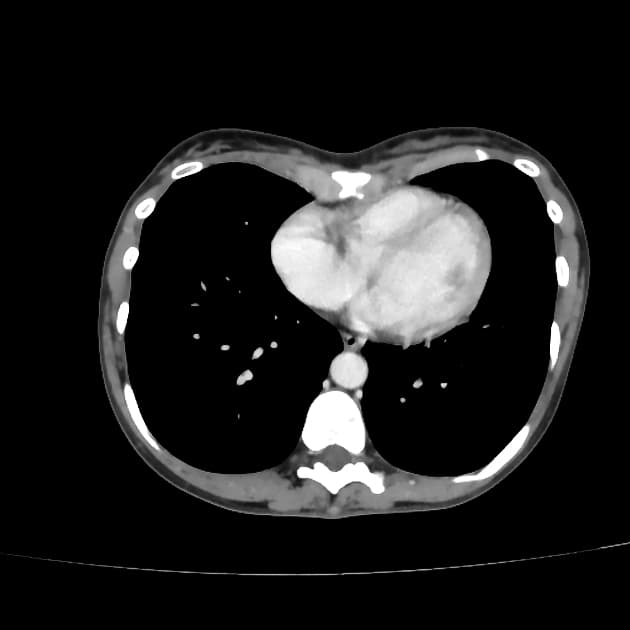

- Cộng hưởng từ (MRI) phát hiện một khối trong trục (intra-axial) lớn, tín hiệu không đồng nhất (heterogeneous signal) ở vùng thùy đỉnh - thái dương trái.

- Khối này gây hiệu ứng chiếm thể tích đáng kể, dẫn đến lệch đường giữa (midline shift), chèn ép sừng chẩm của não thất bên trái (left lateral ventricle occipital horn) và được bao quanh bởi phù vận mạch (vasogenic edema).

- Tổn thương cho thấy các vùng hạn chế khuếch tán (diffusion restriction) và tăng quang không đồng nhất (heterogenous post-contrast enhancement) sau tiêm thuốc cản quang.

- Đặc điểm trên MRI phù hợp nhất với một khối u thần kinh đệm nguyên phát độ cao (WHO độ IV).

- "Cộng hưởng từ cho thấy các đặc điểm điển hình như tăng quang không đồng nhất, hoại tử trung tâm, hạn chế khuếch tán và phù vận mạch lan tỏa kèm hiệu ứng chiếm thể tích."

U nguyên bào thần kinh đệm IDH dạng hoang dại (WHO độ IV) là khối u ác tính nguyên phát phổ biến và nguy hiểm nhất ở não người lớn. Bệnh thường khởi phát nhanh với các triệu chứng như động kinh, suy giảm thần kinh hoặc liệt nửa người. Trên cộng hưởng từ, khối u hiện diện như một khối trong trục lớn, tín hiệu không đồng nhất, tăng quang dạng vòng không đều, hoại tử trung tâm và phù vận mạch lan rộng xung quanh. Hạn chế khuếch tán cho thấy mật độ tế bào cao. Lệch đường giữa và chèn ép não thất phản ánh hiệu ứng chiếm thể tích rõ rệt. Chẩn đoán xác định cần sinh thiết mô và phân tích phân tử: tế bào khối u dương tính với các dấu ấn thần kinh đệm (GFAP, Olig2), và xét nghiệm IDH1 âm tính trong dạng hoang dại. Khác với các u thần kinh đệm có đột biến IDH, ung thư dạng hoang dại thường gặp ở người lớn tuổi hơn và tiên lượng xấu hơn nhiều. Các chẩn đoán phân biệt bao gồm u di căn, ung thư hạch và u sao bào ác tính, nhưng hình ảnh học và miễn dịch mô hóa học giúp phân biệt rõ ràng.